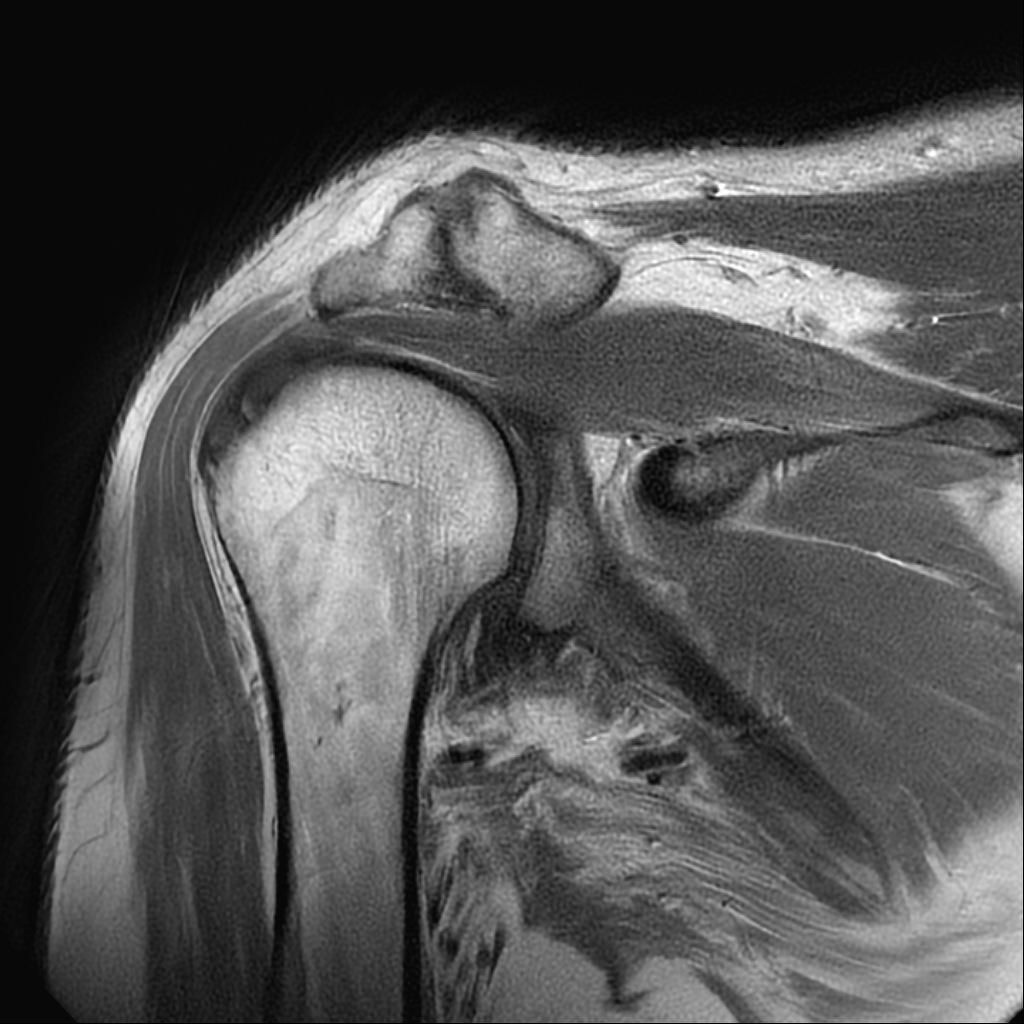

어깨 mri 상태인데 어디가 안 좋은가요?

안 좋다고 하시는데 어디 부위를 말하시는 거죠?

어디 부위인지 알곳 싶습니다.

어깨가 나쁜 부분이 어디죠?

• 2번 째 사진

해당사진으로 많은걸확인할수는없지만 회전근개손상을 의심해볼수있는데요 지속적으로 불편감이있다면 병원에서 검사와치료를받아보시길 바랍니다 감사합니다~

제가 직접 mri를 판독할 수는 없지만 일반적으로 어깨 mri에서 이상 소견이 자주 지적되는 부위는 회전근개 힘줄에 염증, 부분 파열, 손상이 흔합니다 또 견봉 아래 공간으로 충돌증후군이나 염증으로 공간이 좁아질 수 있습니다. 관절순은 탈구 벼력이 있으면 손상 가능성이 있어요 정확한 위치와 정도는 영상의학과 판독결과와 주치의 설명을 참고해야 합니다!

현재로썬 사진만으론 판단을 하긴 어렵지만 회전근개의 손상이 의심 갑니다.

회전근개 주변의 염증이나 손상이 발생하신 것으로 유추해볼 수 있겠습니다.

회전근개 손상은 어깨 관절 주변의 통증과 움직임 제한이 발생할 수 있으며,

완전 파열이 아닌 경우에는 보존적 치료를 우선 적용할 수 있습니다.